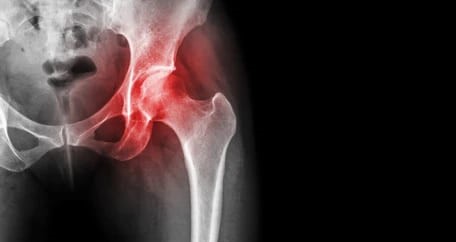

● X-ray(엑스레이)ㅡ 대퇴골두의 모양 변형, 관절 공간의 변화, 뼈 붕괴 여부 등을 확인하는 데 사용됩니다. 하지만 초기 단계에서는 X-ray 상에서 이상 소견이 나타나지 않을 수 있습니다.